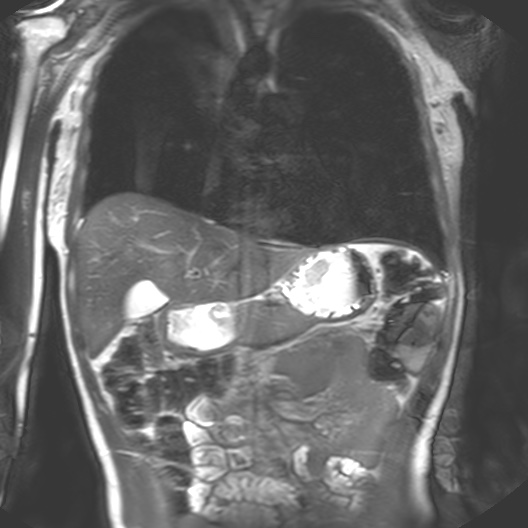

I began my investigation by taking part in MRI trials at the Cancer Centre in 2018 with Dr Heather Fitzke. MRI images confront us with the fact that our bodily materiality acts beyond us and that medical technology shapes our sense of self.

Seeing my organs autonomously pulsing on the monitor in the control room had a pronounced impact on me. It was like looking into a rockpool within my own body. The affecting power of MRI (its power to change our emotions) is in its potential to reveal autonomic bodily functions and diseases which are beyond our control. The data on the screen revealed my autonomous self: peristalsis, bowel movements, digestion, heartbeats and respiration. Through MRI, anatomy is seen as embedded and relational.

I felt a deep sense of fascination with how my organs moved and worked. Haraway’s situated biopolitics argues for an account of the body as an environment, in a state of simultaneous dissolution and formation which I notice in my data. My organs seemed like invertebrates in a rockpool: a squishy pulsing ecosystem. Organs do not operate in isolation but are interconnected. Their autonomous pulsing and motion seemed creaturely and strange in contrast to my numerous encounters with preserved cadavers in the dissecting room. My organs keep me alive yet I have no conscious sense of their functioning. They function beyond me.

Selecting the correct materials to make phantoms was the first step in interacting with the body-machine (interface). I would refer back to my data sculpture and cross-sectional projections from my scans with Dr Fitzke.

Anatomy as a rockpool